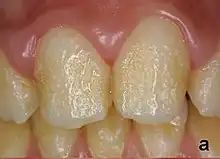

Pitting enamel hypoplasia

Enamel hypoplasia can take a variety of forms, but all types are associated with a reduction of enamel formation due to disruption in ameloblast production.[1] One of the most common types, Pitting Enamel Hypoplasia (PEH), ranges from small circular pinpricks to larger irregular depressions.[2] Pits also vary in how they occur on a tooth surface, some forming rows and others more randomly scattered.[3] PEH can be associated with other types of hypoplasia, but it is often the only defect observed.[4] Causes of PEH can range from genetic conditions to environmental factors, and the frequency of occurrence varies substantially between populations and species, likely due to environmental, genetic and health differences. The most striking example of this is in Paranthropus robustus, with half of all primary molars, and a quarter of permanent molars, displaying PEH defects, thought to be caused by a specific genetic condition, amelogenesis imperfecta.[1]

Each pit is linked to the ceasing of ameloblasts at a particular point in enamel formation. Sometimes, only a couple of ameloblasts stop forming enamel, leading to small PEH defects, with large pits forming when hundreds of these enamel-forming cells stop production.[6] This does not occur in other forms of enamel hypoplasia, such as linear and plane-form, in which all ameloblast activity is affected.[4] Typically with PEH described in archaeological reports, researchers can not specify a cause, with a non-specific stress often concluded. However, in modern clinical studies it is often possible to suggest a cause and these can include the following conditions:[1]